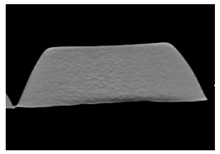

2. Materials and Methods

3. Results